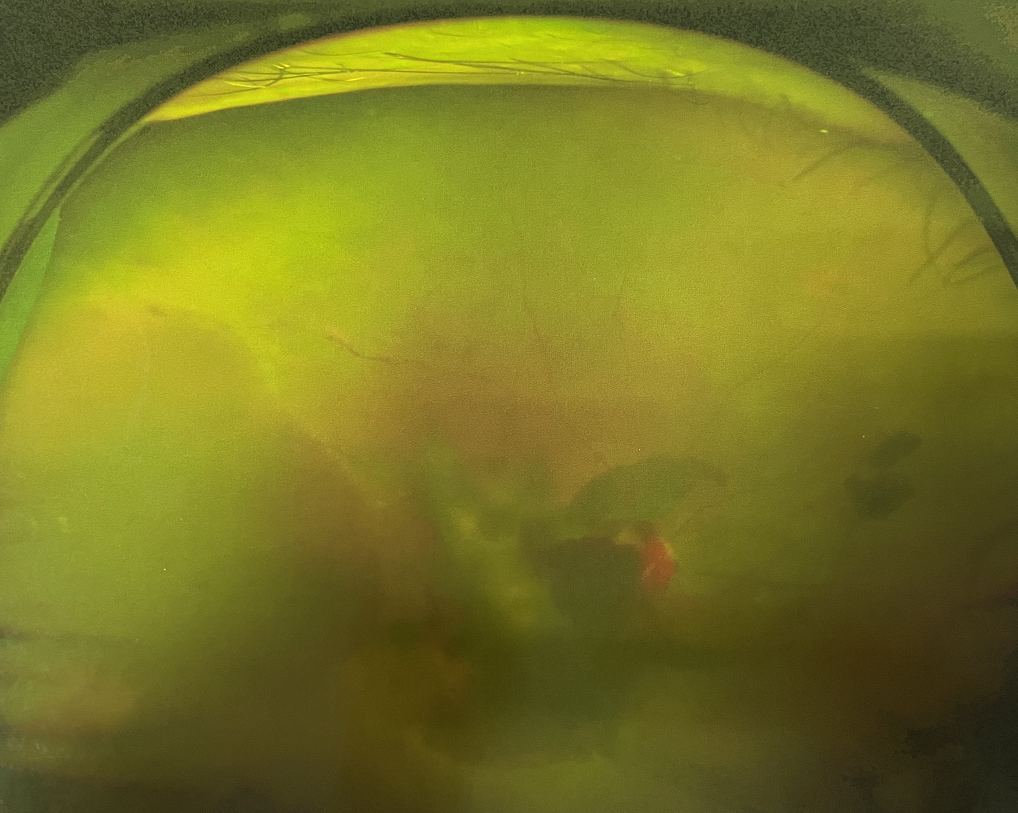

【文章導(dǎo)讀】眼底出血多指玻璃體內(nèi),眼睛更深處的視網(wǎng)膜出血。通常情況下,肉眼難以發(fā)現(xiàn)眼底出血,而且發(fā)病初期眼睛也無(wú)明顯癥狀,只有借助專(zhuān)業(yè)的眼底檢查儀器才能觀(guān)察到異樣。那么眼底出

眼底出血多指玻璃體內(nèi),眼睛更深處的視網(wǎng)膜出血。通常情況下,肉眼難以發(fā)現(xiàn)眼底出血,而且發(fā)病初期眼睛也無(wú)明顯癥狀,只有借助專(zhuān)業(yè)的眼底檢查儀器才能觀(guān)察到異樣。那么眼底出血嚴(yán)重嗎?

眼底出血嚴(yán)重嗎

眼底出血嚴(yán)重嗎?該如何治療?

眼底出血嚴(yán)重嗎?對(duì)于已出現(xiàn)黃斑水腫、視網(wǎng)膜新生血管的患者,根據(jù)眼底血管造影、oct等檢查結(jié)果,給予玻璃體腔注射抗VEGF藥物及激光治療,可以減輕黃斑水腫,使視網(wǎng)膜新生血管消退,以免進(jìn)一步發(fā)生玻璃體出血、視網(wǎng)膜脫離等嚴(yán)重并發(fā)癥的出現(xiàn)。對(duì)于玻璃體出血者,傳統(tǒng)認(rèn)為玻璃體出血3-6個(gè)月不吸收再進(jìn)行手術(shù)干預(yù),但近年來(lái)因?yàn)轱@微手術(shù)設(shè)備及玻璃體切割技術(shù)已非常成熟,故對(duì)于1個(gè)月不吸收的玻璃體出血者就可以考慮手術(shù),即手術(shù)時(shí)機(jī)應(yīng)該具體情況具體分析,因人而異。